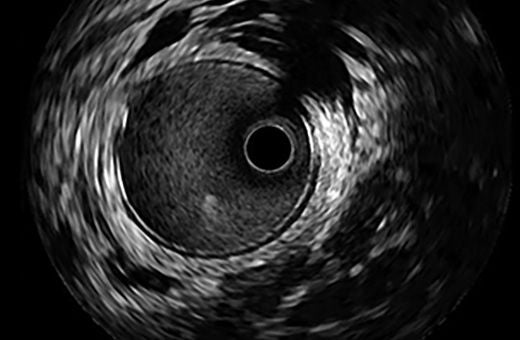

Philips Volcano Revolution Imaging Catheter 45MHz

IVUS image of inside a coronary vessel using the 45MHz Philips Volcano Revolution Platinum catheter

Axial resolution: 50 µm